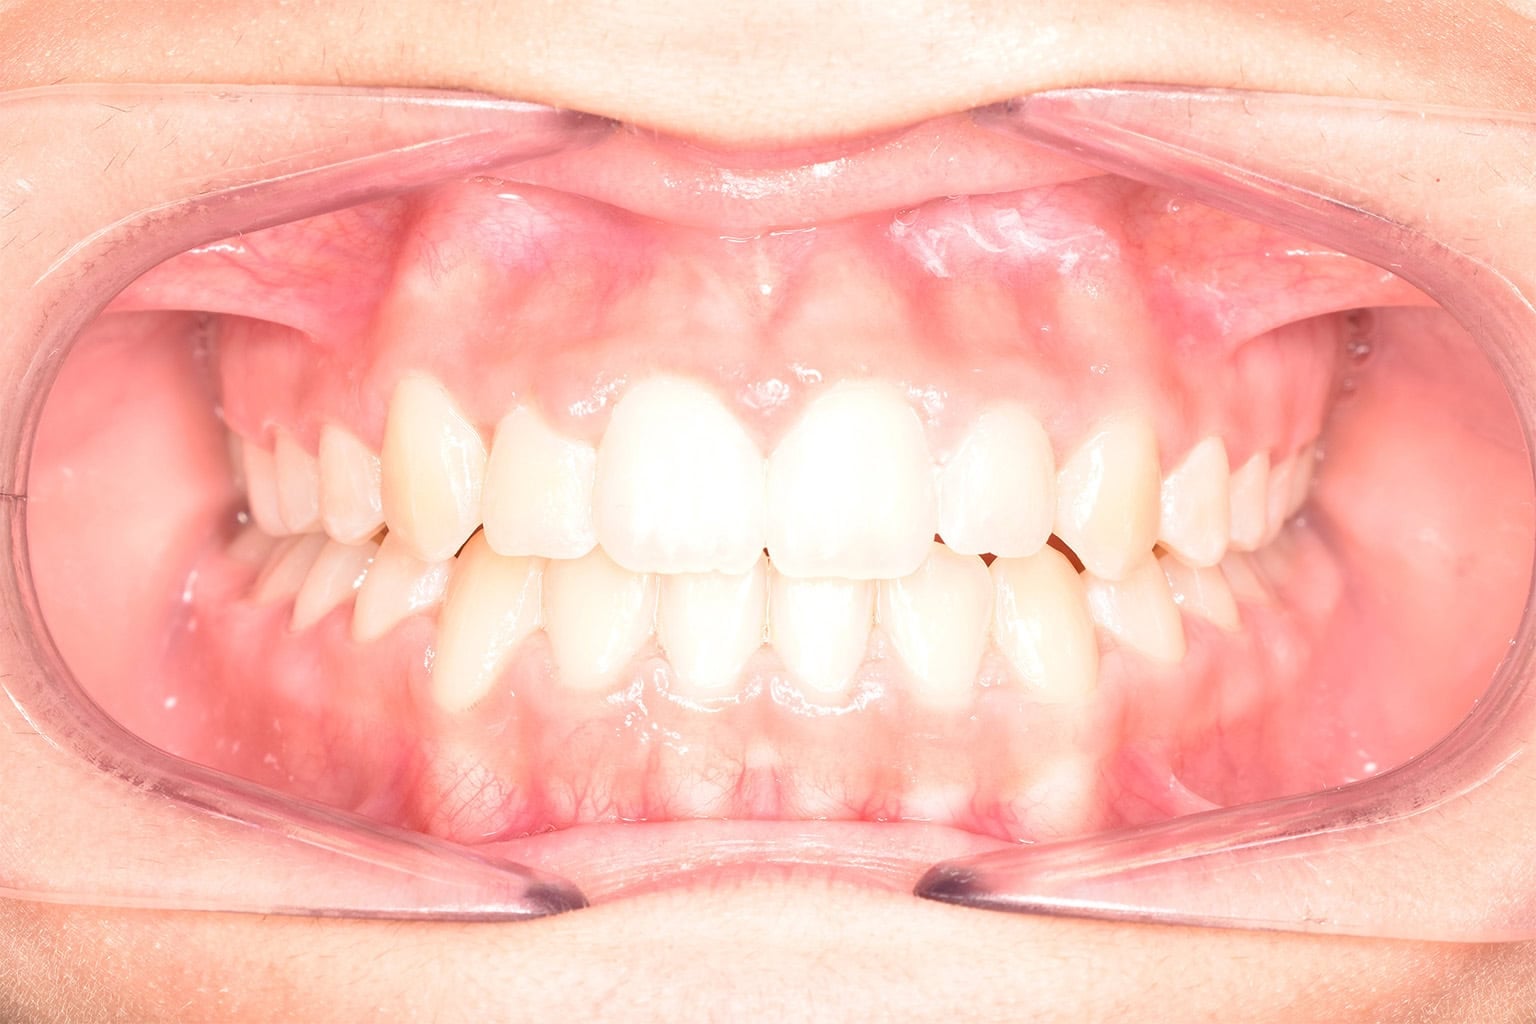

Jede Behandlung bei TIEFBLAU Kieferorthopädie ist so individuell wie der Mensch dahinter. In unserer Vorher-Nachher-Galerie zeigen wir Ihnen echte Behandlungsergebnisse aus unserer Praxis in der Kölner Südstadt: Schonend erzielt, präzise geplant und mit dem Anspruch, den wir seit über 40 Jahren an jede Behandlung stellen.

Die Bilder geben Ihnen einen Eindruck davon, was moderne Kieferorthopädie leisten kann, ob bei Kindern, Jugendlichen oder Erwachsenen.